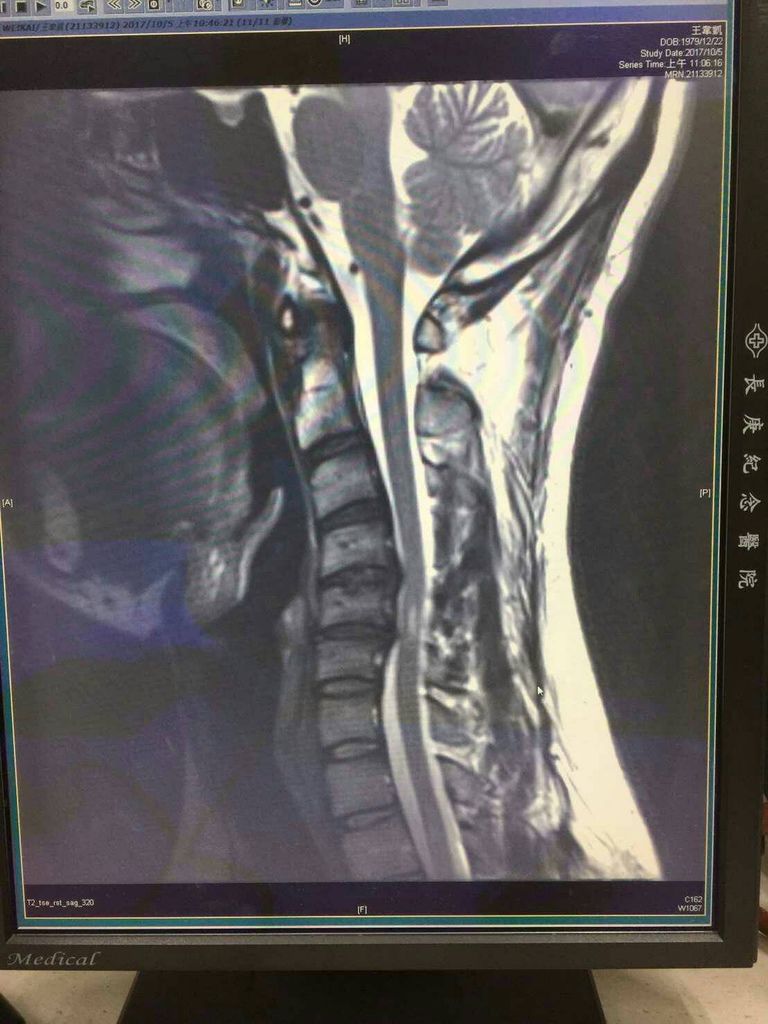

上圖是一張算是中度以上的頸椎退化的X光片而醫生或是推拿整骨師最常說明的診斷就是椎間盤突出、骨刺、或弧度太直等等~~,片中的男性年齡約30多歲,會分享出來其實是有一個很不一樣的地方。早在2~3年前他就來過中心但只有做過2-3次,當時也都是根據椎間盤突出、骨刺、弧度太直等等問題為處理方向但效果未見理想,往後的一年多期間也是到處看醫生但都未見改善,所以一直游離在是否手術的困擾中,直到有一次在朋友口中的分享所以再次回到我的工作室,這次的處理就不在單單的針對頸椎5.6節的退化做處理。其實退化是一個過程和結果,但其實我們更應該把處理方向擺在造成加速退化的成因,頸椎之所以會退化、突出最主要的原因就是壓力集中在單一節上,以這例子來說就是頸椎5.6節,而壓力集中原因就在於錯誤的姿勢習慣、固定姿勢停留太久,肌肉間前後左右張力不平衡等等~,也因此在處理時不應當只在退化本身。所以這次除了針對弧度的調整外,也一併放鬆了頸部前後肌張力的不平衡,就這麼一次這個麻木2年左右時間的手,居然改善了許多表示不麻了剩背部較緊繃,頸椎退化是事實但如果只看問題本身那真的無法挽救了,但如果做的是改變成因那就是充滿希望,寫這篇文章最大的用意都是希望受問題困擾的患者,一定要懂得跳脫制式化的醫學觀念,才能有更多復原的機會。捷安物理治療所 發表在 痞客邦 留言(0) 人氣(481)